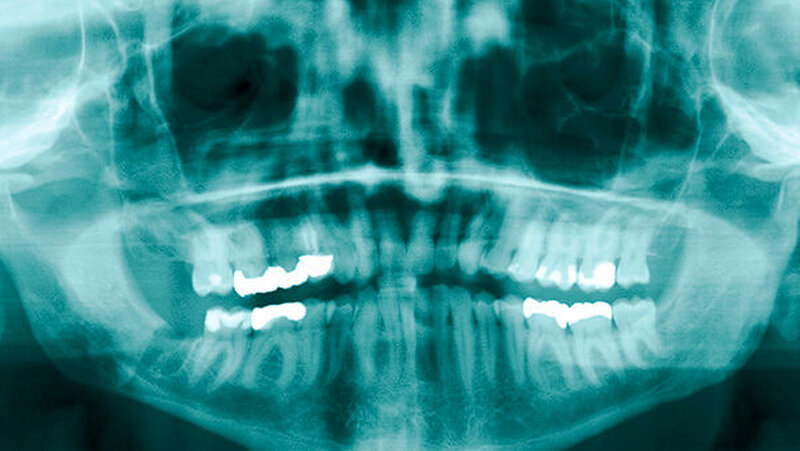

Da von transoral keine direkte Sicht ins Spatium submandibulare möglich war, wurde das Wurzelfragment 48 mit dem Zeigefinger palpiert und mit einer stumpfen gebogenen Klemme und der Fingerbeere entfernt (Abbildung 7). Das kleinere Kortikalisfragment ließ sich digital identifizieren und in gleicher Weise entfernen. Nach Reposition der Weichteile erfolgte ein mehrschichtiger Wundverschluss mit Einzelknopfnähten, zirkumdentalen Nähten und einer Tabaksbeutelnaht regio 37 zur Refixierung des lingualen Mukoperiostlappens. Der postoperative Verlauf gestaltete sich unter perioperativer Antibiose komplikationslos. Die postoperativen radiologischen Kontrollaufnahmen (Orthopantomogramm, Zahnfilm) ergaben keinen Hinweis auf ein verbliebenes Zahnfragment.